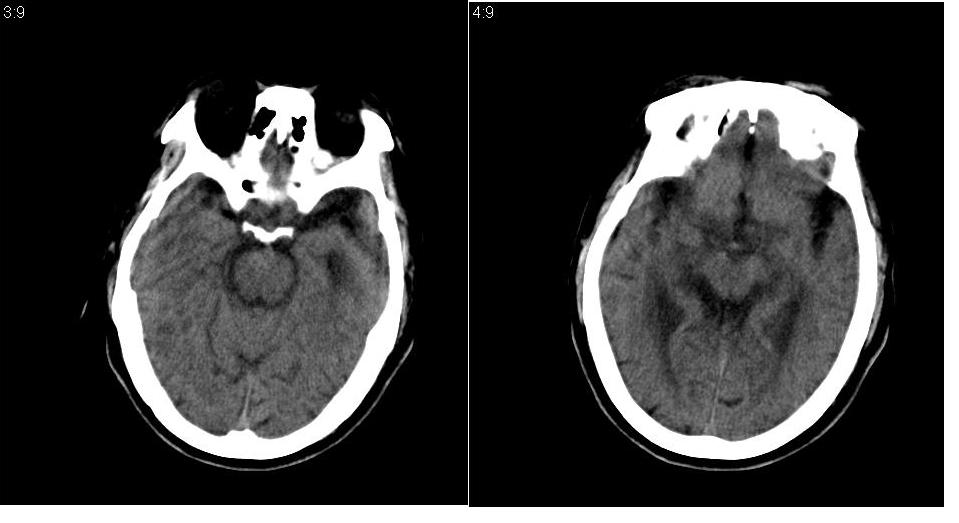

男 73岁,肢体活动不灵多年。

颅内多发梗塞灶,左基底节区囊腔形成。

左侧基底节区软化灶,双侧基节区多发性腔梗。

脑萎缩,脑白质病,左基底节区梗塞软化灶。

皮层下动脉硬化性脑病伴多发腔隙性脑梗塞及软化灶。

左右侧脑室前后角对称性低密度区,边缘模糊,脑沟,脑池增宽,脑室扩大,左侧基底结区见多个低密度病灶

诊断:1皮层下动脉硬化性脑病

2左侧基底结区腔梗